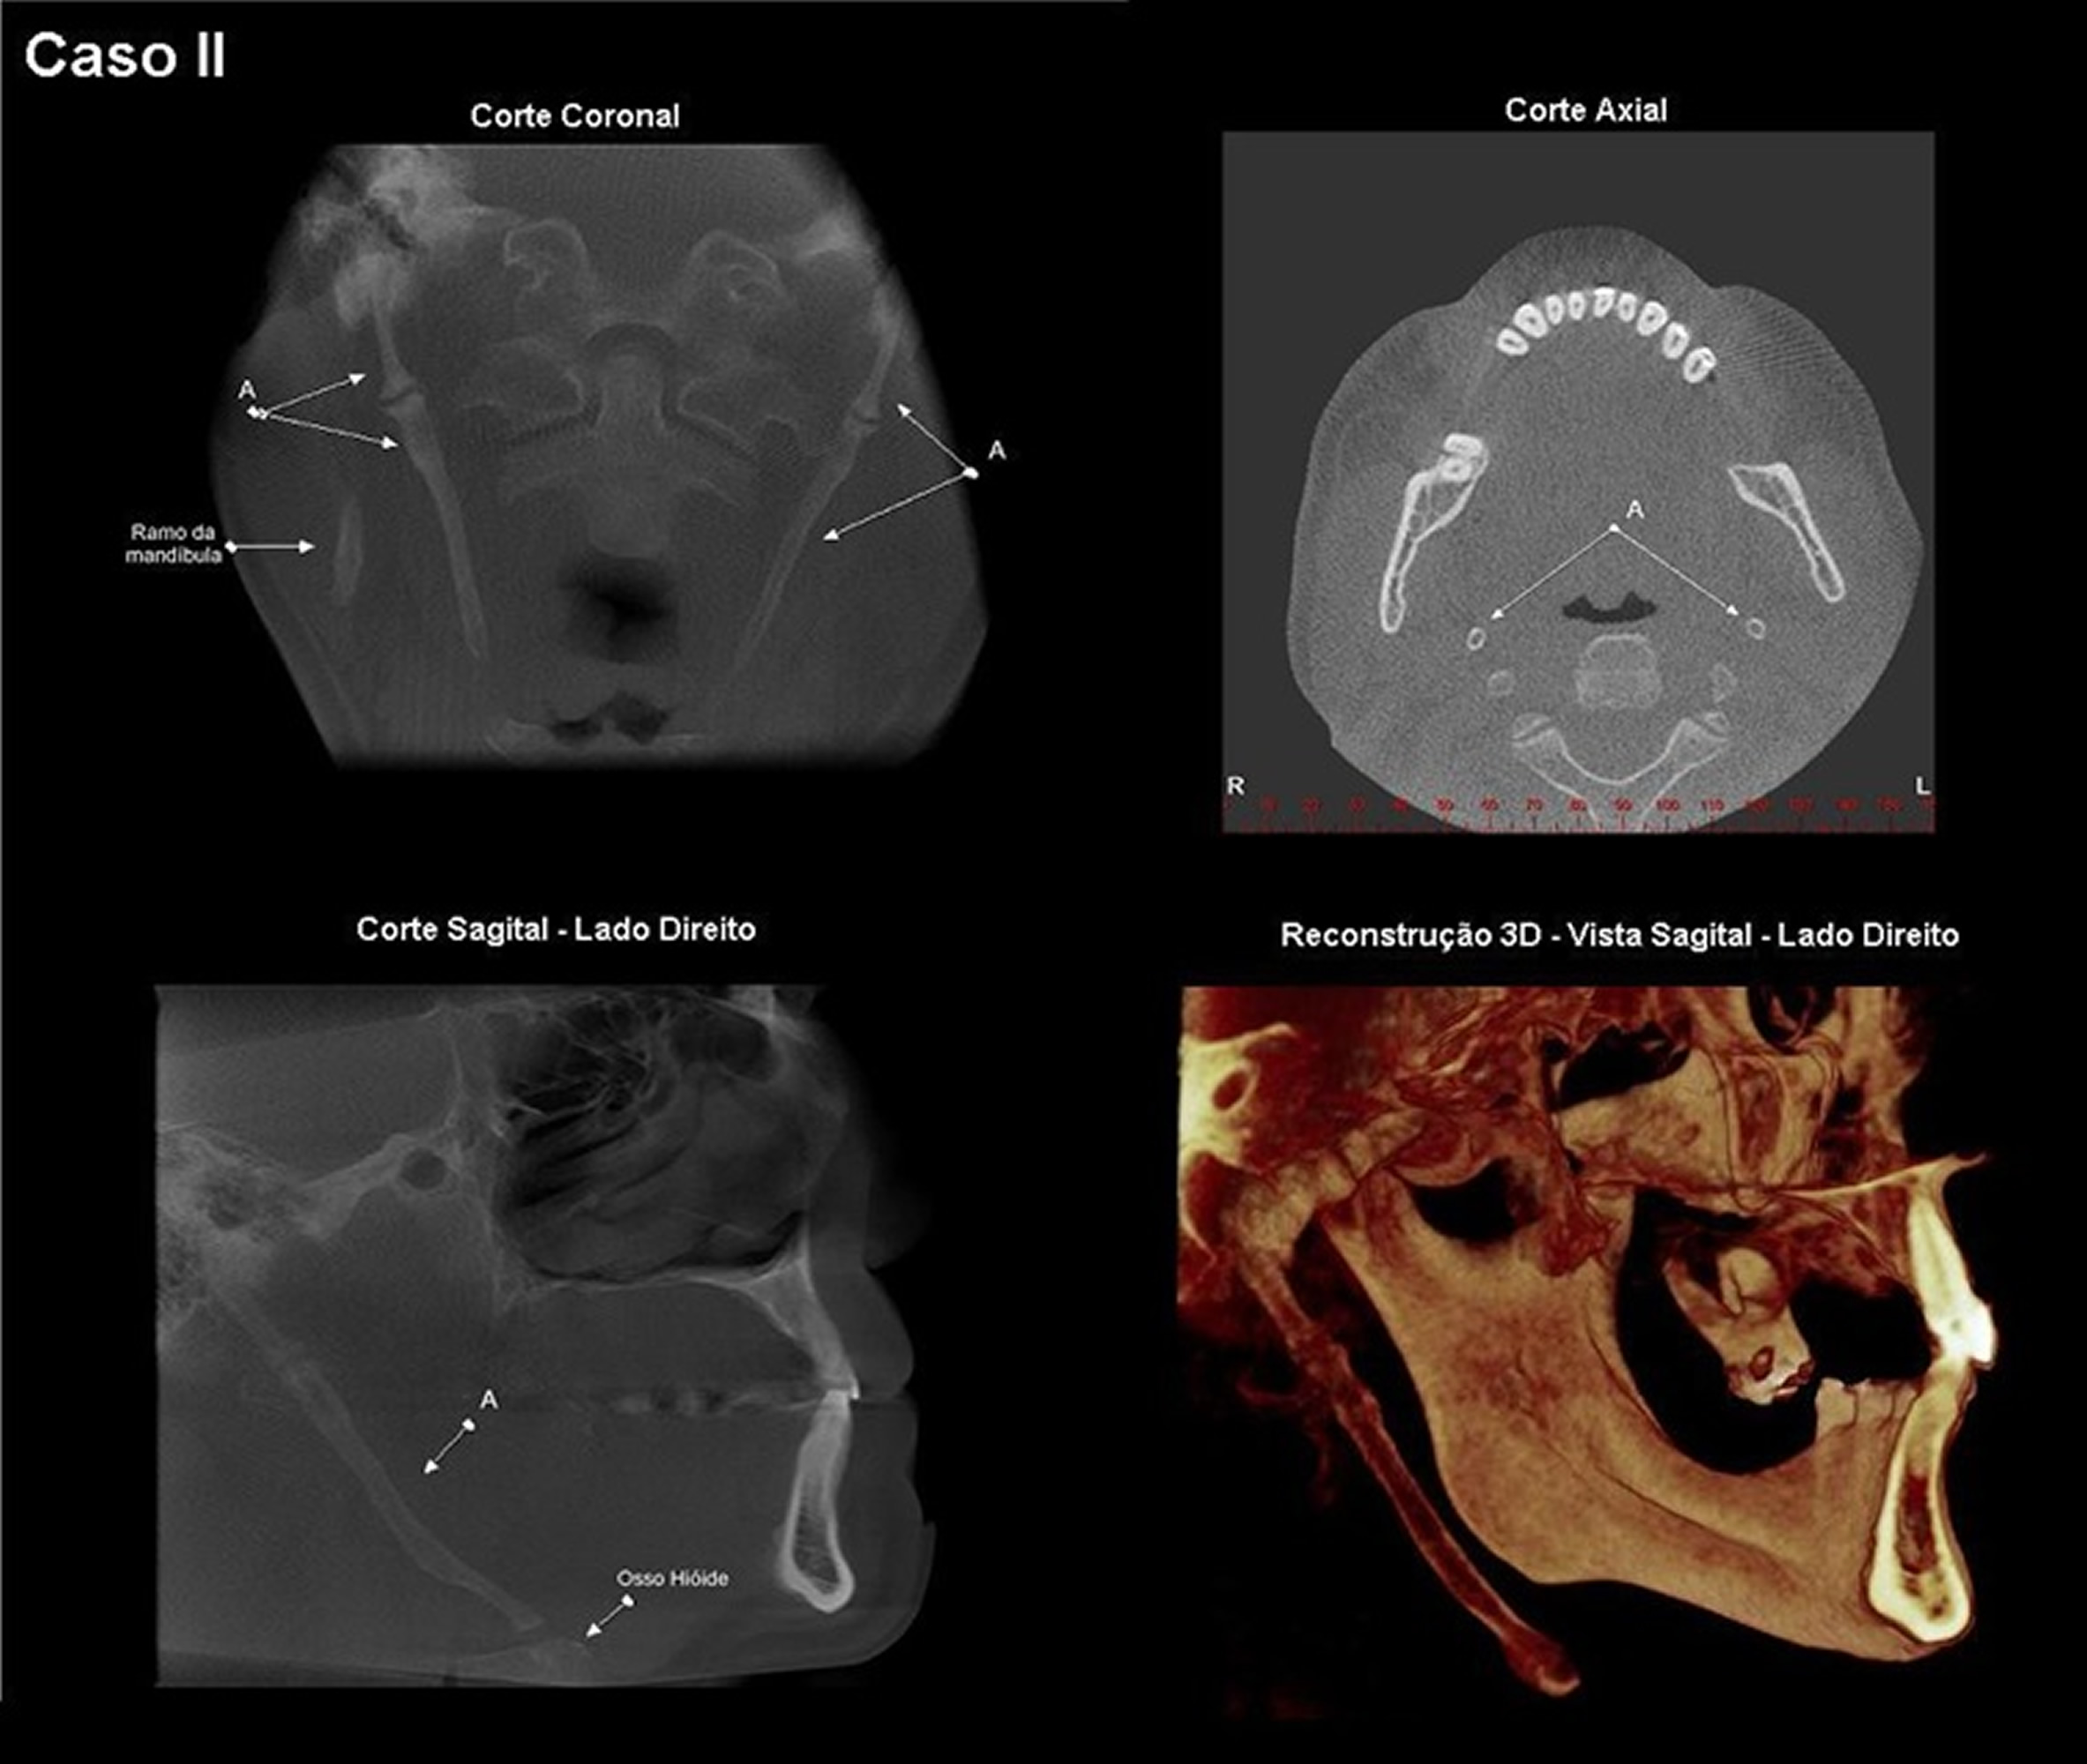

Cortes Axial Coronal Sagital E Reconstrucao 3d Da Tomografia Download Scientific Diagram

www.researchgate.net